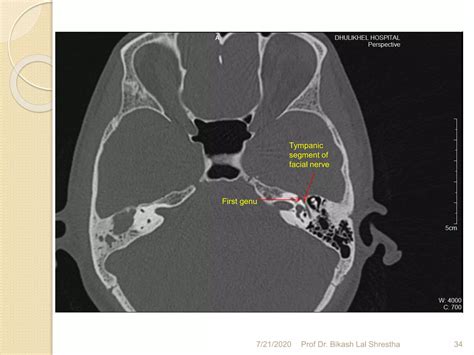

• Facial Nerve Palsy: Damage to the facial nerve, which runs through the temporal bone, can cause paralysis of the facial muscles.

Facial Nerve Palsy Abnormalities in the facial nerve canal Facial muscle weakness or paralysis